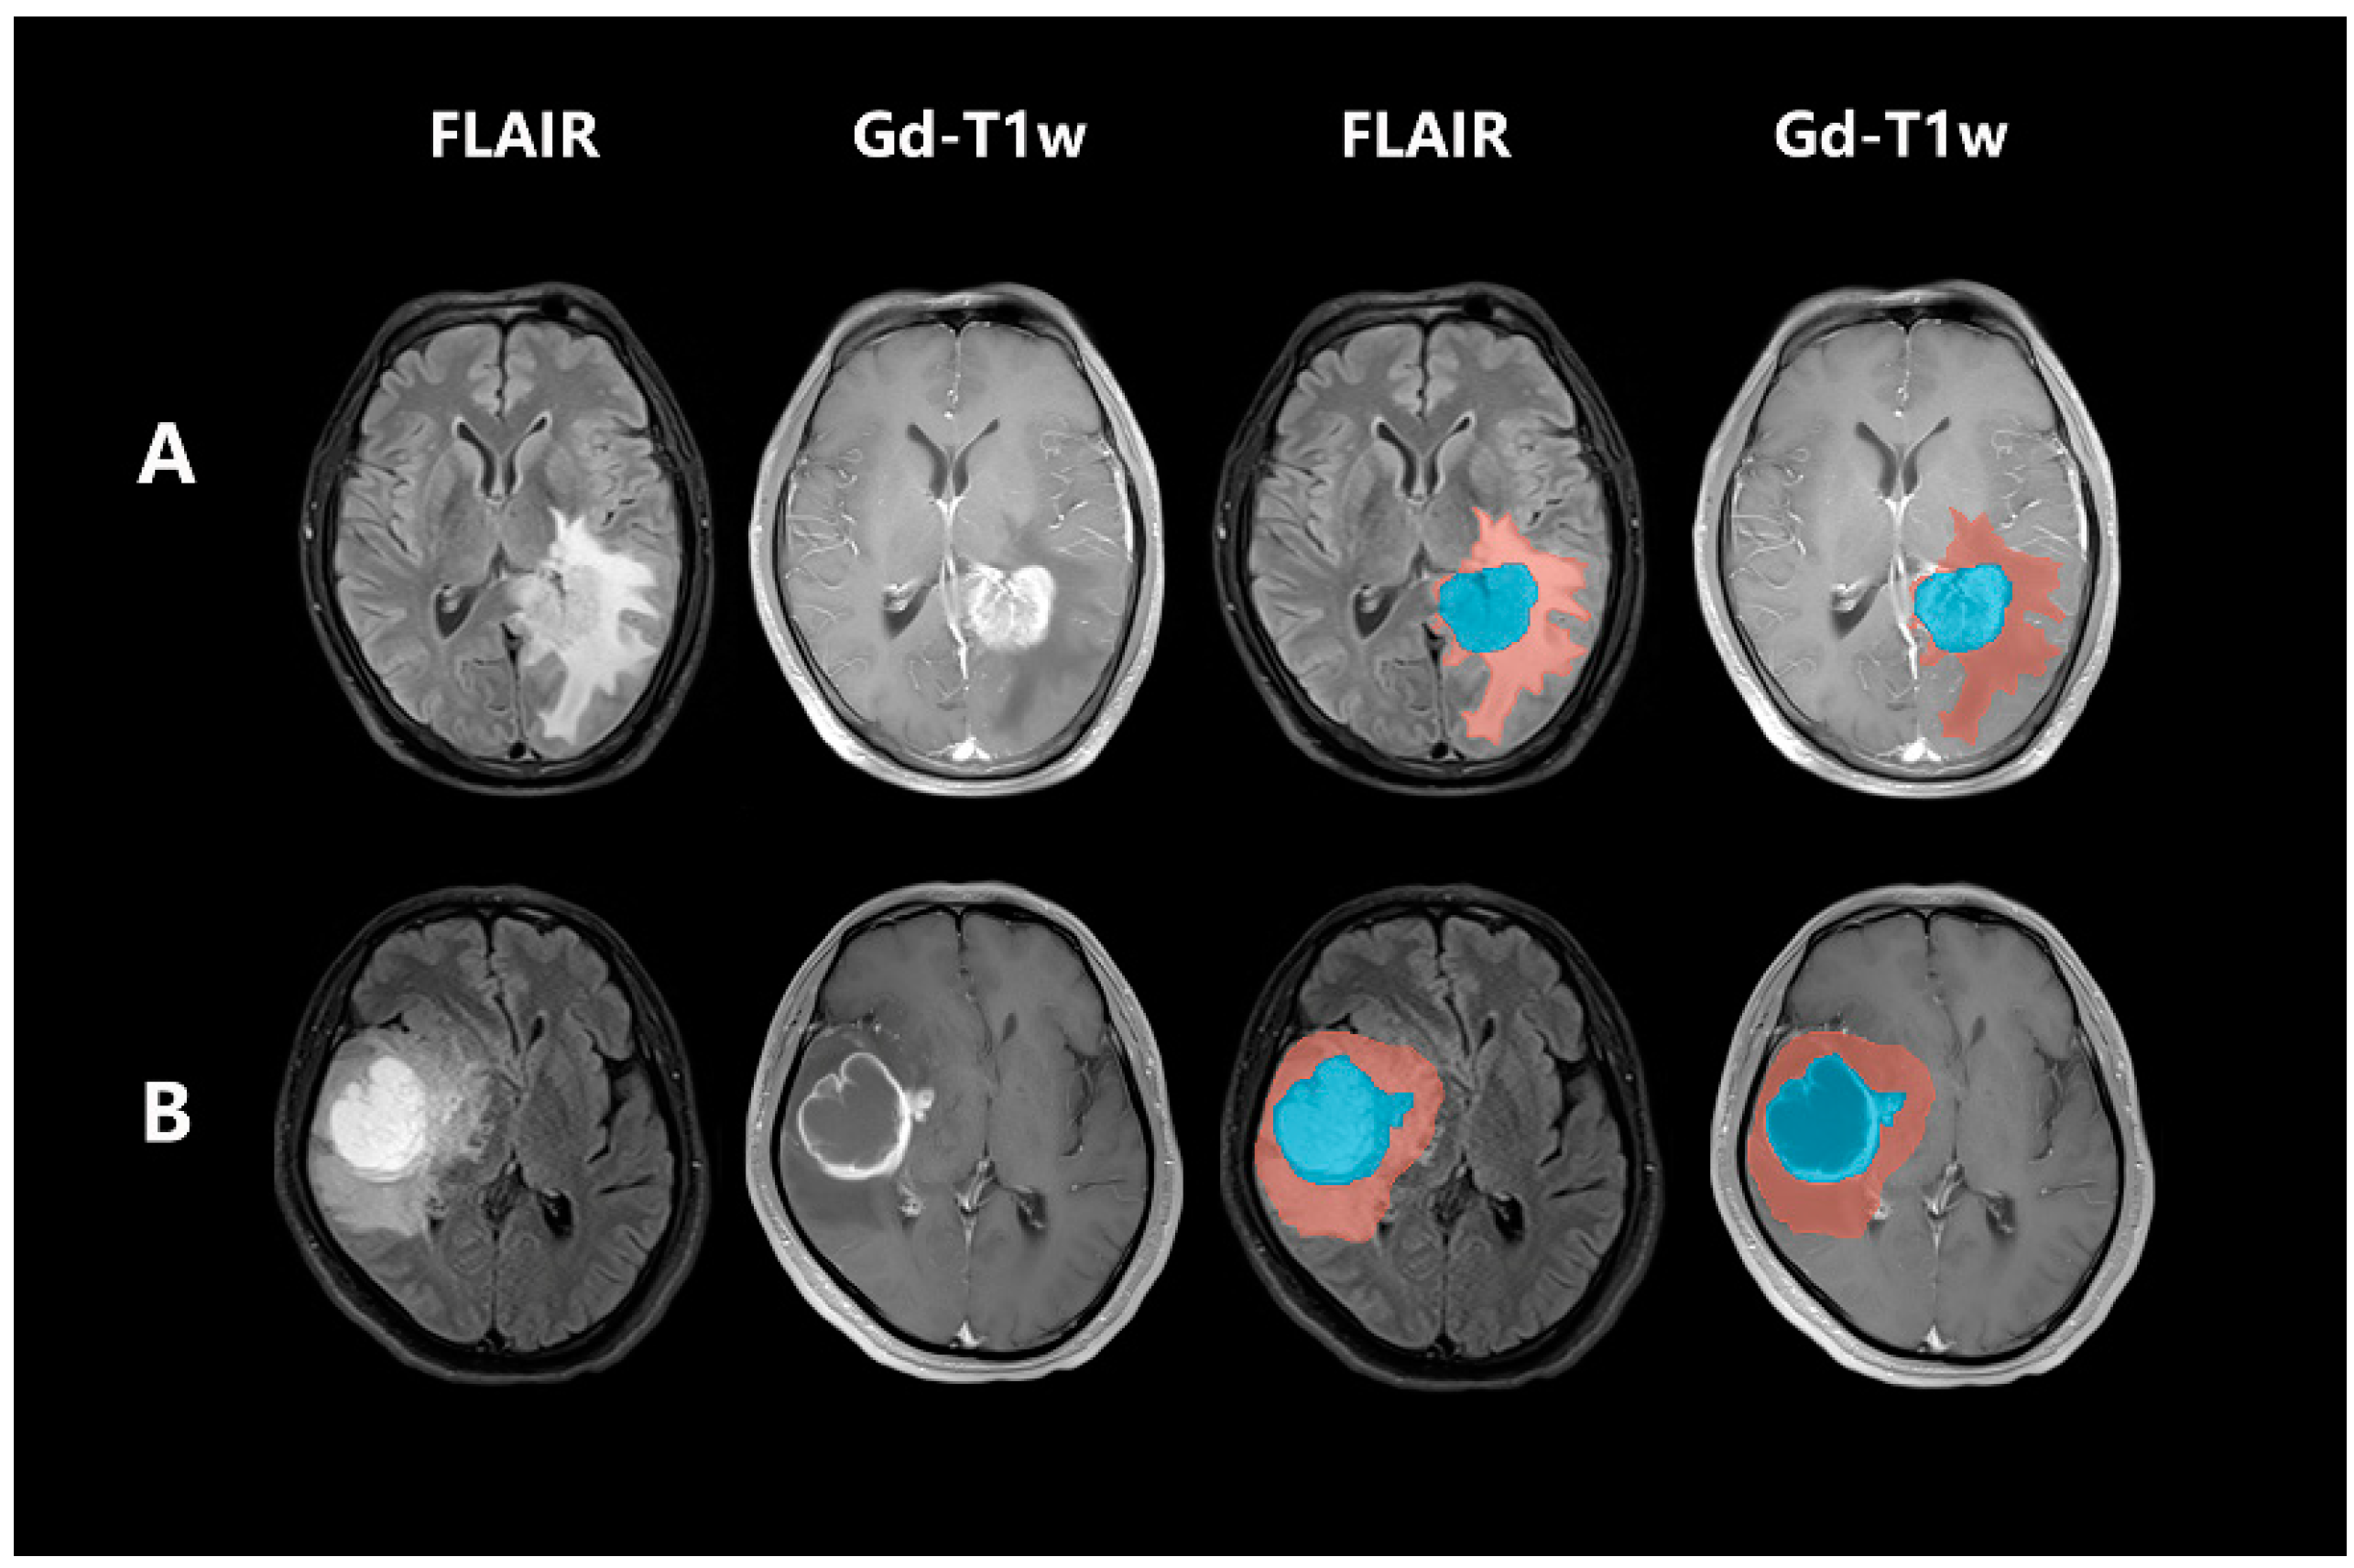

2.4. Post-Acquisition Preprocessing and Segmentation